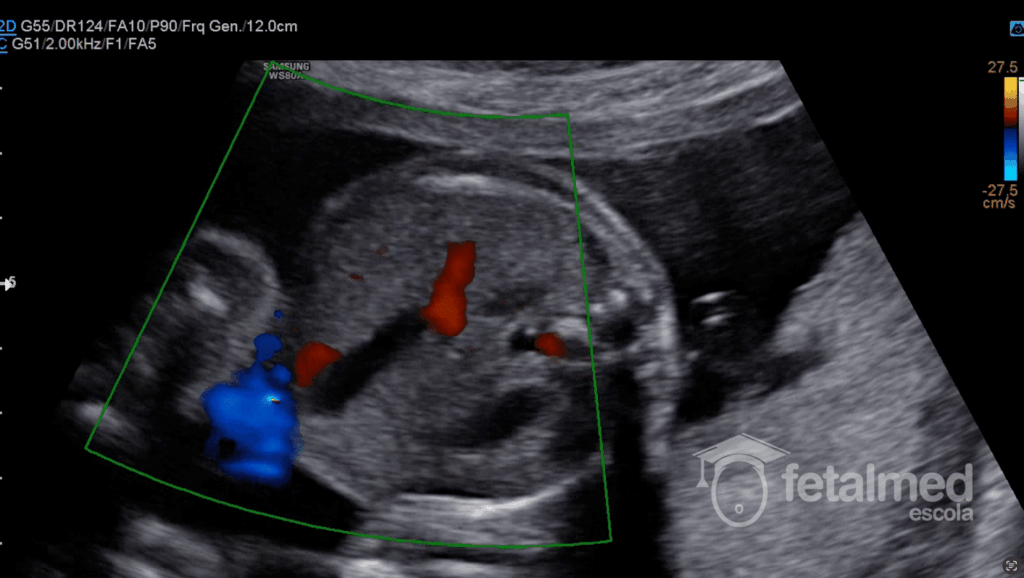

Achados Ultrassonográficos

O diagnóstico pré-natal da VUDP é relativamente fácil por meio de exames ultrassonográficos. Os critérios de diagnóstico incluem o curso anormal da veia porta em direção ao estômago e a localização da veia umbilical no lado direito médio da vesícula biliar. A visualização desses achados ultrassonográficos permite o diagnóstico da VUDP.

O diagnóstico da Veia Umbilical Direita Persistente pode ser feito pela posição da veia umbilical e da vesícula biliar. Em casos alterados a veia umbilical fica mais à direita da vesícula biliar. Ainda é possível notar que a curva da veia umbilical é para a esquerda, e não para a direita como em casos normais.